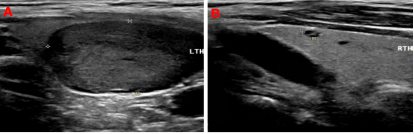

99mTc-MIBI甲状旁腺SPECT/CT融合显像图:图1+2冠状位、图3+4矢状位、图5+6横断位,提示功能亢进甲状旁腺组织(十字线交叉处)。随后的超声提示:双侧甲状旁腺区多断面超声扫查未见明显异常占位性病变;双侧甲状腺结节,其中左侧叶内一枚33mm×19mm低回声、边缘光滑、内无强回声结节。颈部B超图:AB(纵切面)分别显示甲状腺左叶、甲状腺叶;左叶内一低回声结节。